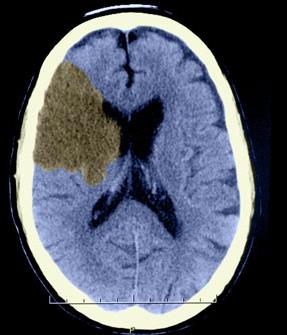

Epidural hemorrhage: Blood accumulates between the dura mater and cranium due to damaged blood vessels.

Subdural hemorrhage: Blood pools between the dura mater and arachnoid mater.

Cerebrovascular accident (CVA, or stroke): Blood supply to a brain region is cut off, causing loss of function in that area.